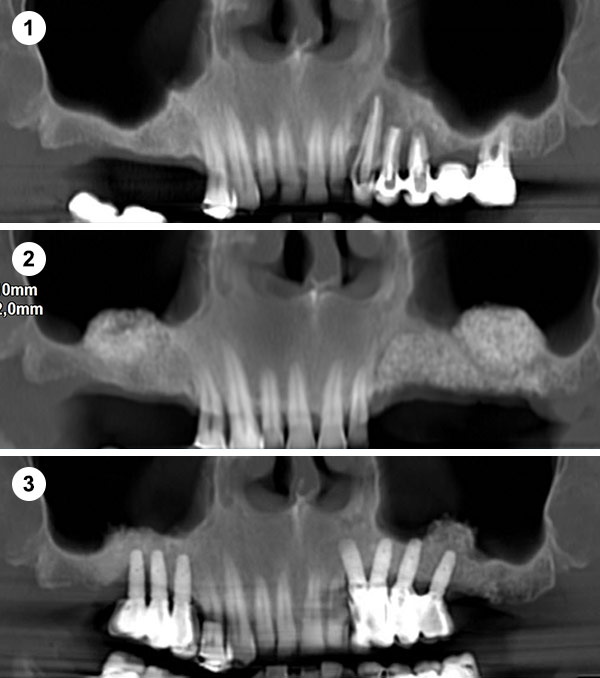

Esta técnica consiste en aumentar la altura y anchura del hueso en los maxilares introduciéndonos en el seno para conseguir una base ósea que permita la colocación de implantes.

Es un procedimiento sencillo que se realiza con anestesia local. Se practica una pequeña incisión a la altura de las raíces de los molares y premolares del maxilar superior, se crea una ventana en el hueso para acceder a la cavidad sinusal y se eleva la membrana para colocar un injerto de hueso en el suelo del seno maxilar.

Cuando no hay hueso ni distancia suficiente entre el maxilar superior y el seno (altura menor a 5 mm) que imposibilita la colocación de implantes.

Indicaciones: Se emplea en casos donde la cantidad de hueso residual es muy escasa (<5 mm) o cuando se necesita un aumento significativo del volumen óseo.